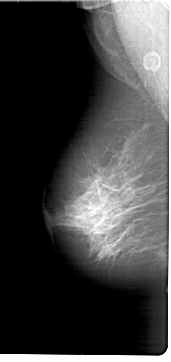

A_1847_1.LEFT_CC

FILE: A_1847_1.RIGHT_CC.OVERLAY

TOTAL_ABNORMALITIES 1

ABNORMALITY 1

LESION_TYPE MASS SHAPE ARCHITECTURAL_DISTORTION MARGINS SPICULATED

ASSESSMENT 4

SUBTLETY 4

PATHOLOGY BENIGN

TOTAL_OUTLINES 1

BOUNDARY